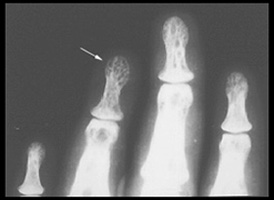

PUNCHED OUT LYTIC LESIONS LACY TRABECULAR PATTERN DEFORMING LESIONS

Focal osteolytic lesions in the fingers are the most common abnormality. The lesions in this patient are larger than usual.

Osteolysis has left a lacy trabecular pattern in this phalanx (arrow)